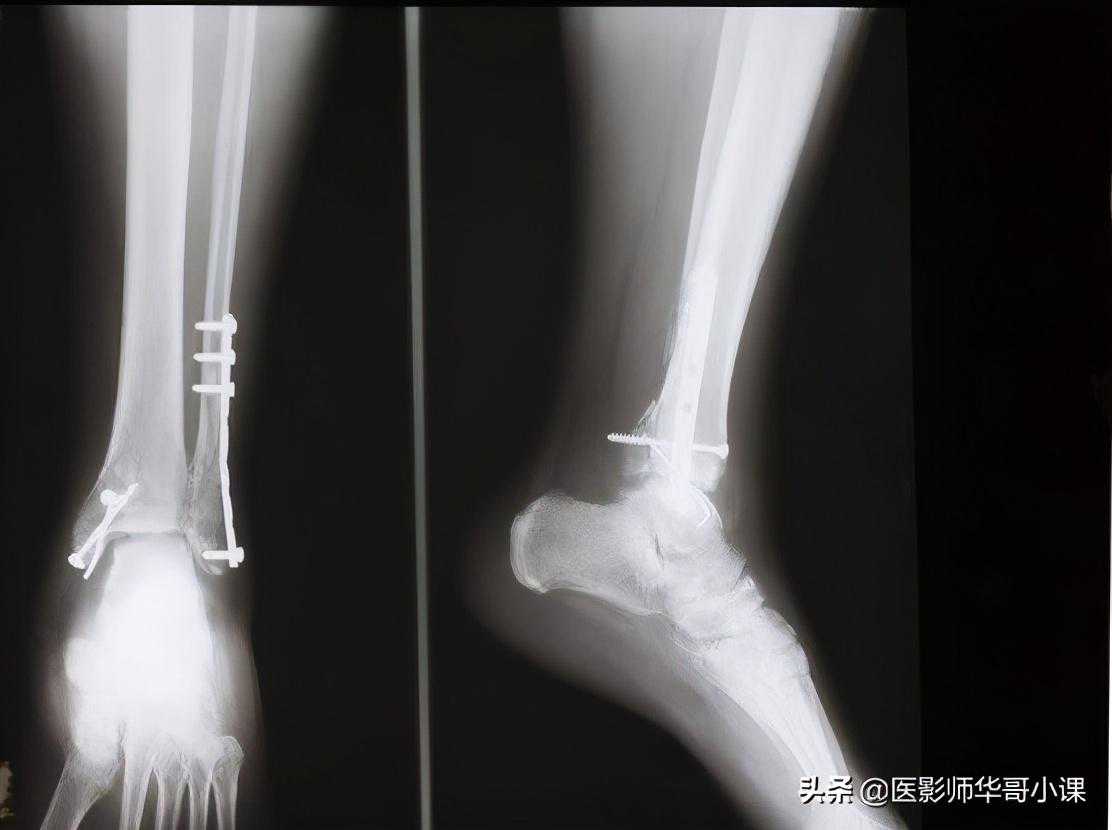

第五节小腿与膝

1.胫腓骨骨干和尺桡骨骨干一样,由于骨间膜的附着而皮质可变得较厚和不整齐,在胫骨轻度外旋的前后位片上,胫骨前嵴重叠在外侧皮质上,好像皮质增厚。

2.胫骨结节约于1115岁之间骨化,其正常变异很多,化骨核的结构形态多样,有时是胫骨近端化骨核的一部分,有时是单独存在的或呈分节状,相当结节处的骨干部有时有一条深的切迹,在前后位片上表现为骨质缺损,这些现象有时与胫骨结节的骨折酷似,鉴别十分困难,但局部软组织肿,压痛和侧位片上结节向前脱离是较可靠的鉴别点。

15.胫骨远端可能出现一个单独分离的内踝化骨核,腓骨外踝部也可有一个单独的化骨核。

16.胫骨骨干远端外侧面面有一条沟槽即腓骨切迹。